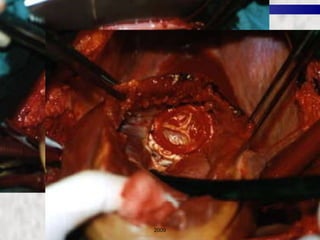

CORONARY ARTERY BYPASS GRAFTING (CABG) 2009

CORONARY ARTERY BYPASSGRAFTING (CABG) 2009